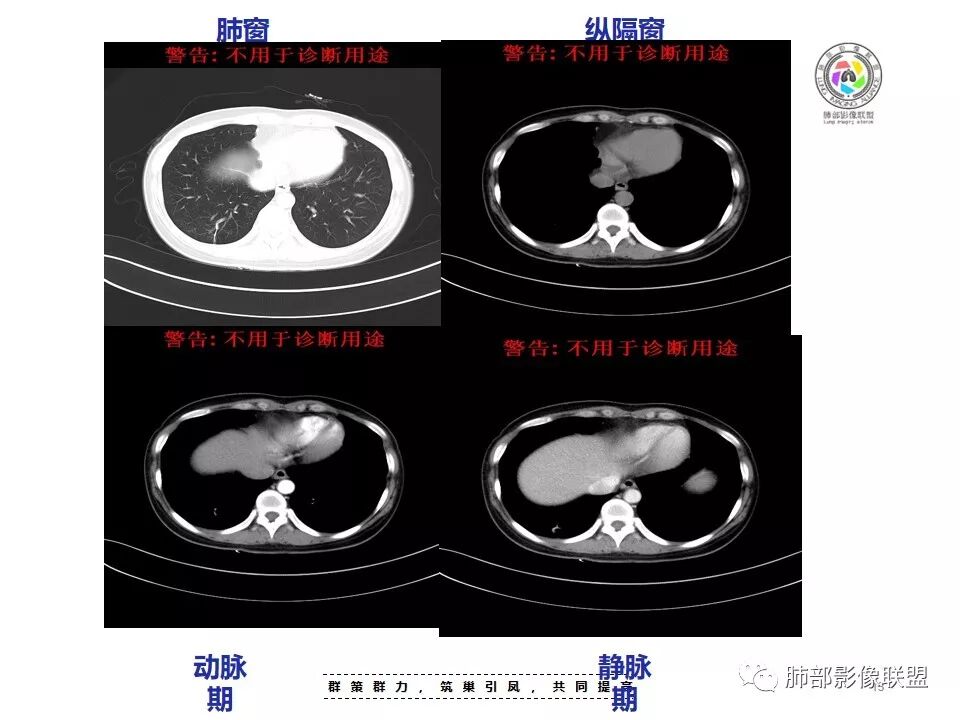

胸部CT:右肺上叶尖段脊柱旁实性结节灶,宽基底与胸膜接触,可见平直征、软毛刺、棘突、空泡,中心片状坏死,周围磨玻璃影边界不清,胸膜增厚、糊墙。增强呈环形强化。右肺下叶实性小结节,见长毛刺、胸膜牵拉。综合考虑:炎性病变,结核可能大。鉴别隐球菌、腺癌。

胸CT:右肺上叶尖段膜下实变病变,病灶边缘毛刺、棘突征、U型征、平直,病灶边缘可见毛玻璃影,纵隔窗可见病灶与胸膜间可见低密度,增强可见病灶强化,病灶内可见低密度区,静脉期较动脉期貌似强化明显,考虑肉芽肿性病变,结核?但病灶周围部分存在膨隆,恶性不除外。

右肺上叶胸膜下结节,边缘有平直、刀切征及桃尖征,病灶与胸膜呈宽基底,胸膜糊墙,这些征象均指向良性病灶;病灶内可见液化坏死区,壁相对厚,强化较显著;病灶周围较大范围磨玻璃影,边缘模糊,淡薄柔和,未见卫星结节或树丫,提示为一个急性渗出,这是符合炎性病灶脓肿形成的。

换个角度看,右肺上叶这肿瘤符合吗?如此小范围肿瘤灶很少能够在影像上观察到如此明显的坏死,内壁还如此光整?即便是鳞癌,更遑论腺癌及小细胞癌等,不要忘了这是中青年女性患者。

结核易形成空洞,但周围渗出如此明显,没有卫星灶,内壁如此圆整,厚壁强化如此明显,都很难与常见的结核灶关联起来。

会是什么感染?临床症状相对和缓,脓肿单发的,经验上尤以G-杆菌感染较为多见,如肺炎克雷伯杆菌等。

二.右肺下叶病灶

右肺下叶胸膜下结节判断难度较大。

病灶边缘以收缩为主,长大棘状突起,胸膜牵拉凹陷明显,说明病灶纤维化明显,倾向炎症或腺癌,但病灶GGO模糊,且未见异常强化,按理考虑慢性炎性可能较大。可以穿刺活检除外腺癌可能。粘液腺癌很少有如此显著的牵拉能力。